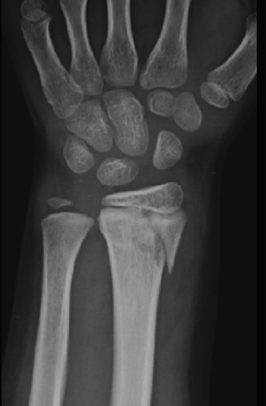

Name this Classification of fracture in relation to the growth plate of a pediatric wrist?

Salter-Harris Type II (metaphysis with extension into epiphyseal plate) (MC)